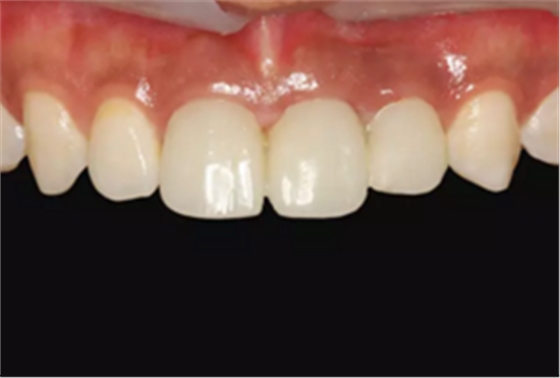

图1 术前微笑像

图2 术前口内像

图23 最终修复后即刻口内像

图25 最终修复后复查口内像